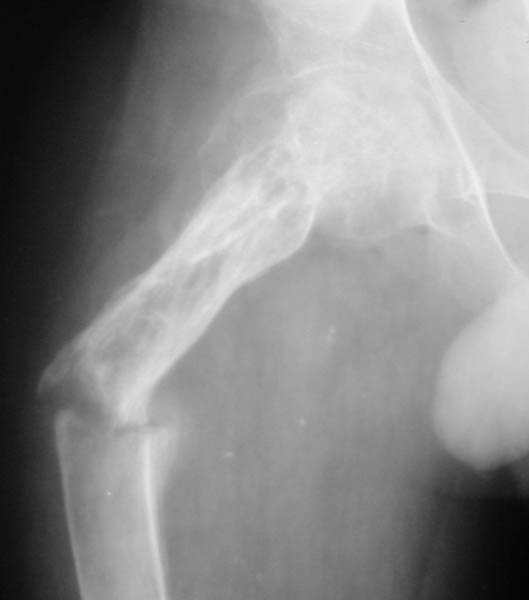

Мальчик, 14 летЖалобы на боли в правом бедре, резкое ограничение активных и пассивных движений в тазобедренном и коленном суставах справа, вынужденное положение правой ноги. Диагноз: Хондрома проксимального отдела правого бедра, состояние после внутриполостной резекции и аллопластики, закрытый патологический перелом проксимального отдела правого бедра со смещением В 2001 г. - хондрома проксимального отдела правого бедра. Операция - внутриполостная резекция, аллопластика. В течение 2 лет - 2 патологических перелома (СВ, гипс). 23.04. - закрытый патологический перелом проксимального отдела правого бедра.Патогистологическое исследование от 06.05.: остеобластома, диагноз в пользу агрессивного варианта.Тактика лечения?С уважением,А.В.ВладзимирскийДонецкий НИИ травматологии и ортопедииДонецк, Украина

Нельзя ли показать другую проекцию, а то в приложении две фотографии одной и той же рентгенограммы.